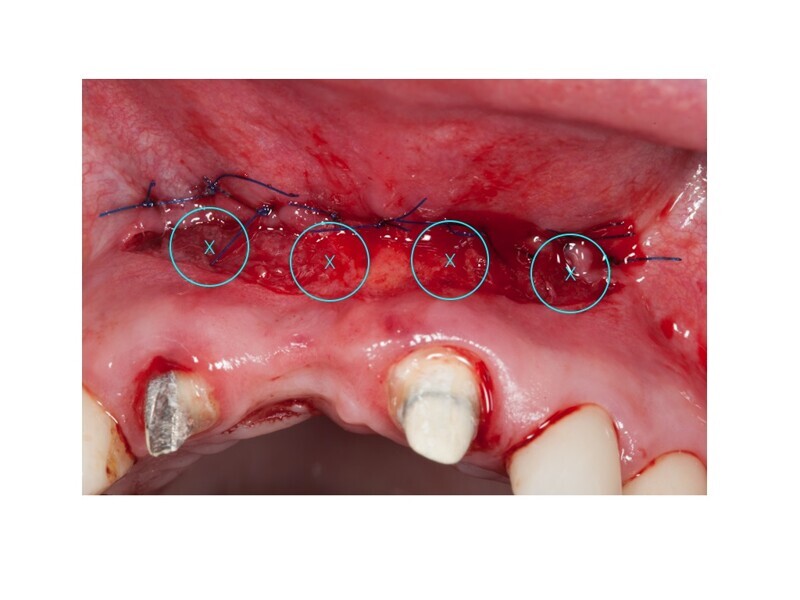

Biomodulacja laserem Nd:YAG z użyciem głowicy Genova®